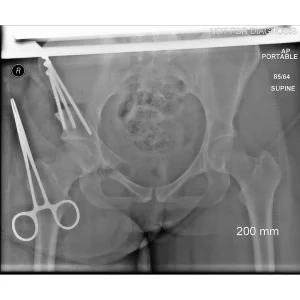

During a PAO, the surgeon carefully cuts the bone around the hip socket and repositions it to provide better coverage of the femoral head. The socket is then fixed in its new position using screws. The goal is to improve hip stability, reduce pain, and preserve the patient’s natural hip joint.

• Screws shown securing the acetabulum in its new position

Screw Removal

In most cases, the screws are left in place. However, if they cause irritation, removal can be considered after the bone has healed, which is typically 9-12 months after the initial PAO.